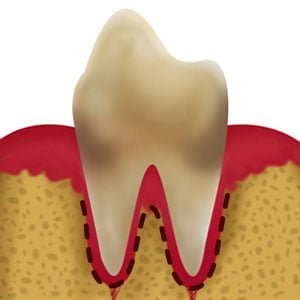

Sente Saudável

Placa

Tártaro

Gengivite

Periodontite

Periodontite Avançada

No estágio inicial da doença periodontal, há poucos sinais de um problema. No primeiro estágio, há apenas uma pequena alteração da cor dos dentes.

Os pais podem pensar que isso é normal ou que não representa um problema. Na maioria dos casos, a doença nesse estágio deixa de é tratada.

A consequência é que a doença vai avançando de um estágio para outro, piorando a saúde oral de seu pet que venha a sofrer com a condição.